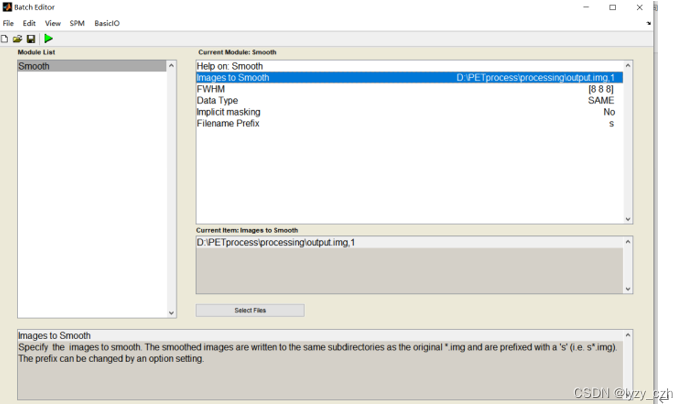

6)最后一步进行8mm的平滑

依次选择所有步骤如下一共5个步骤:

注意在Image Calculator的Expression输入是固定的因此可以直接在这里输入如下:

4、生成batch脚本

选择保存脚本的路径